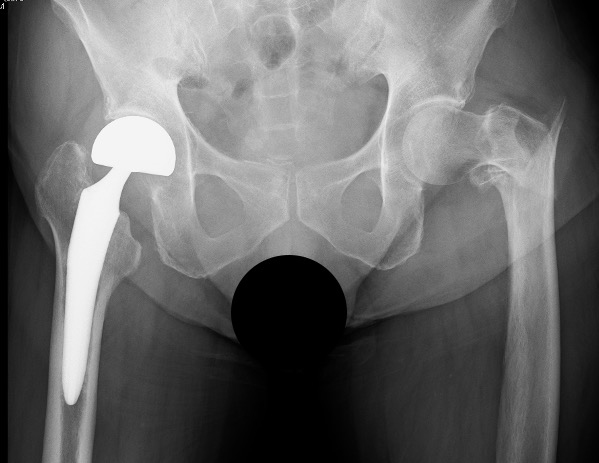

総合整形外科

リハビリテーション科